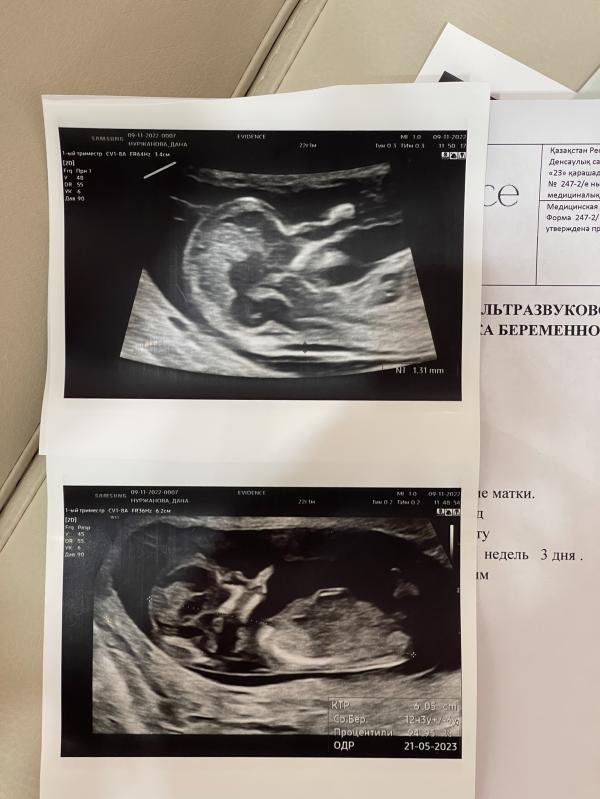

Забеременеть получилось сразу; страхов было очень много из-за двурогой матки и полного удвоения матки ( две матки).

На 8-й неделе появилось гематома, начала принимать дюфастон и магний. На 13 неделе из- за аномалии развития перевели в роддом на ЭКСПО.

Уже забыла на которой неделе гематомы на узи не было, если не ошибаюсь через несколько недель после первого скрининга. Из-за внутреннего волнения на УЗИ ходила стабильно раз в две недели. Слушала сердечко и расслаб...